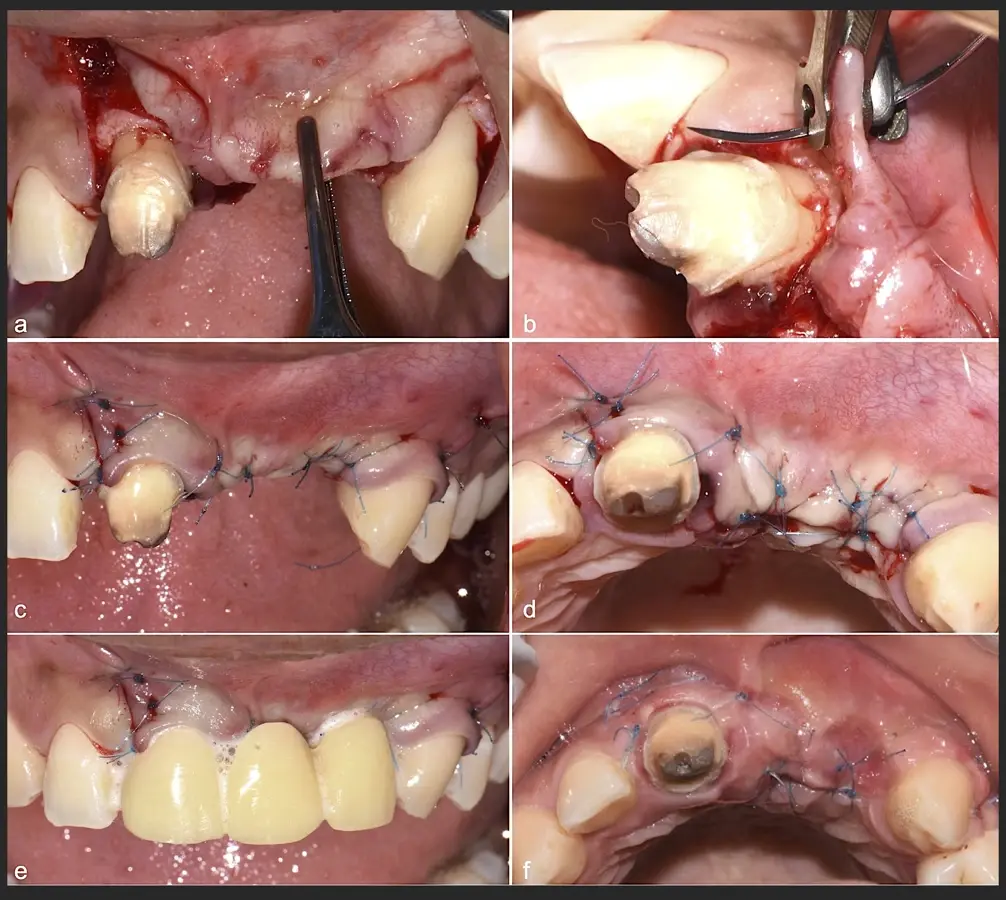

Figura 45. Afrontamiento de colgajo y sutura (a - e). Control a los 7 días postquirúrgico (f).